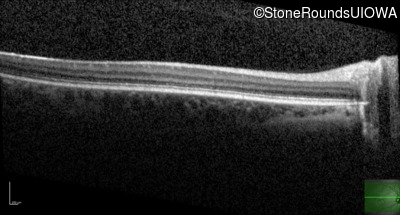

AR Stargardt Disease (IIA)

Age at visit:

14 years

OD

OS

20/125 -2

20/25 +2

OCT Stack

AR Stargardt Disease

ABCA4

Gly1961Glu GGA>GAA

Asp1613 del1gA

AR